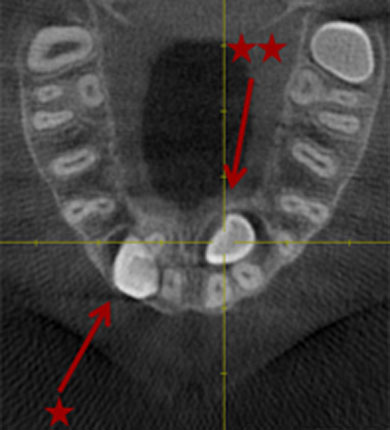

Lagebestimmung von verlagerten Zähnen

Im normalen Röntgenbild kann die genaue Lage nicht sicher festgestellt werden.

In unserem Fall hier lag ein Zahn zur Lippe hin (*) und ein Zahn im Gaumen (**). Mit diesen Informationen können wir minimalinvasiv und sehr schonend operieren!